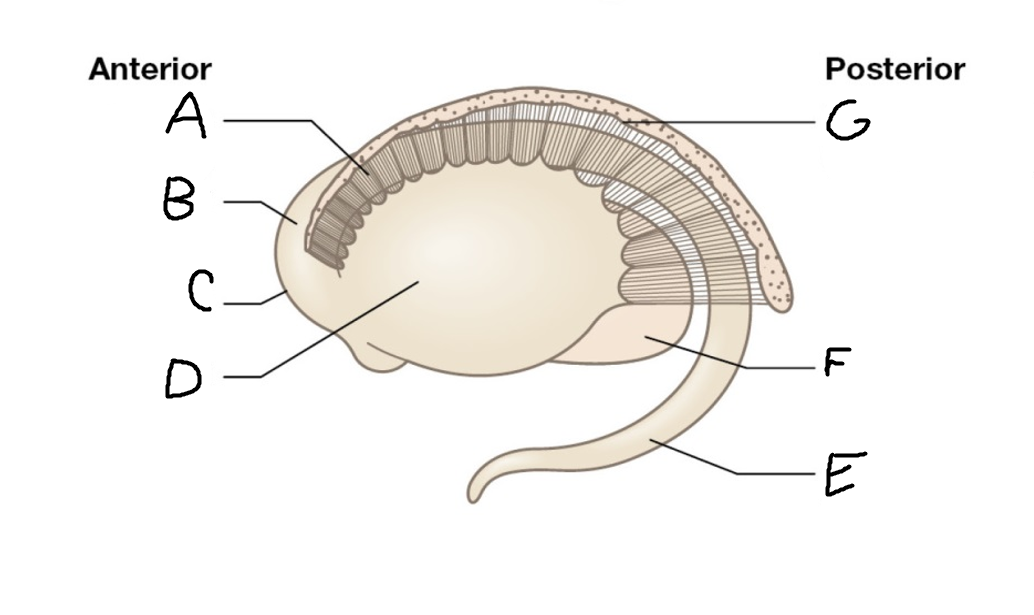

caudate nucleus head

A

Putamen

B

caudate nucleus tail

C

Lateral ventricle

D

caudate nucleus body

E

internal capsule

F